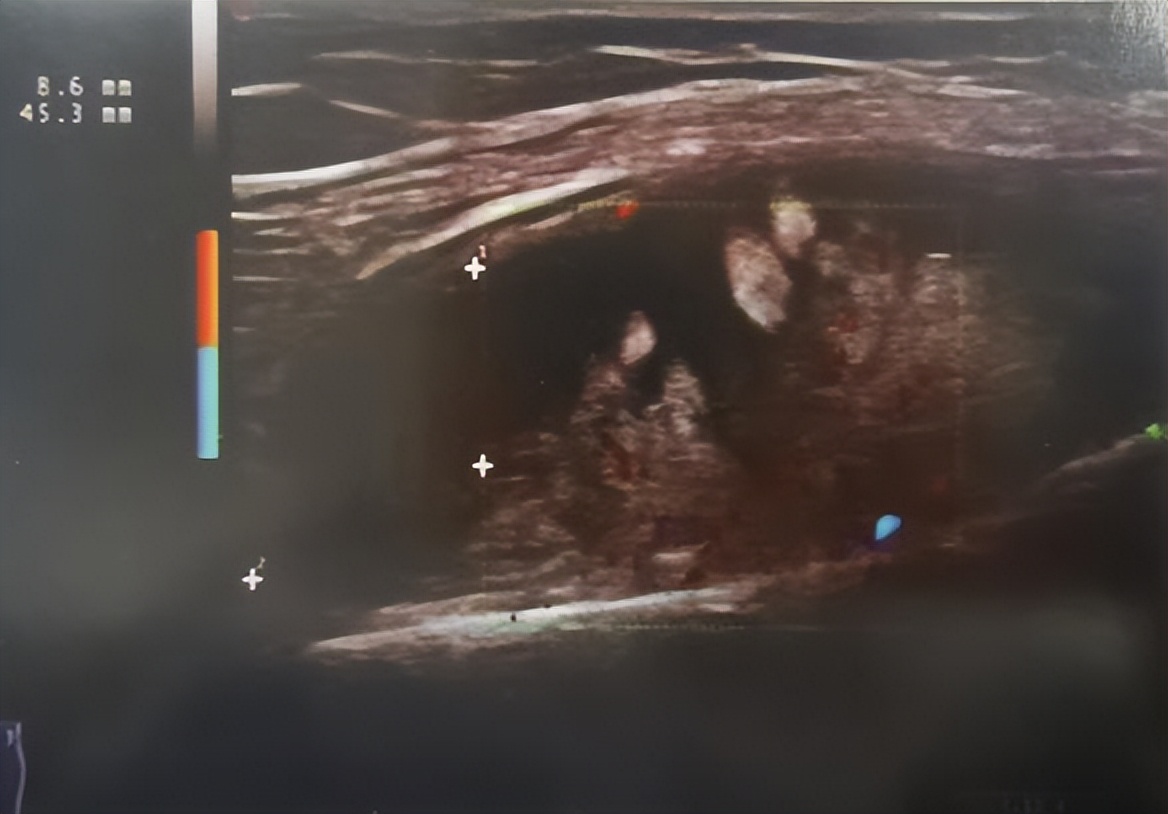

肌骨超声(Musculoskeletal ultrasound,MSKUS),是指应用于肌肉骨骼系统的超声诊断技术,目前,肌骨超声已成为与X线、CT和MRI并列的肌肉骨骼系统主要临床影像诊断技术之一。

肌骨超声在风湿病的诊断与治疗中起着十分重要的作用。与其它影像学检查相比,肌骨超声在肌肉骨骼系统检查方面有自己独特的优势,凭借其无创、便捷、无辐射、无明确禁忌症、检查费用低、实时动态显像、重复性强等特点,目前已广泛应用于临床。那么肌骨超声能做些什么呢?

1、超声可定量评价滑膜增生、滑膜炎、积液程度;

2、鉴别关节腔内积液与滑膜增生;

3、病变累及关节周围肌腱时,可见肌腱增粗、腱鞘内积液、滑膜增生等;

4、超声还可显示骨侵蚀、骨赘、附着点病变等;

5、超声引导下可进行介入治疗,精准定位的同时还能有效避免一些并发症。介入超声属于微创技术,相当于用一次精确的小手术来替代大手术,减少患者的射线辐射及创伤。